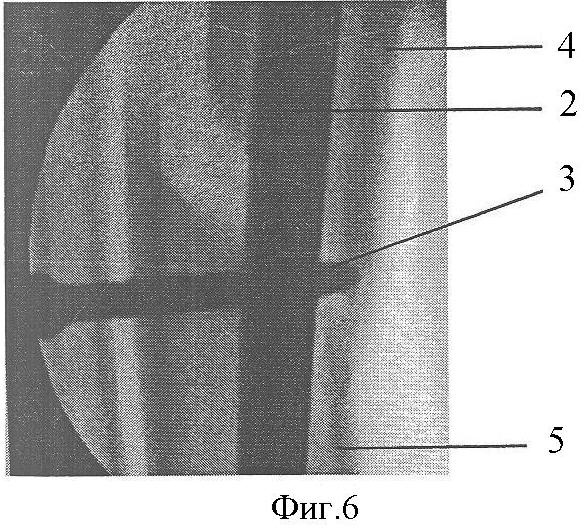

Фиг.6 и Фиг.7. Интраоперационные снимки на экране электронно-оптического преобразователя: момент репозиции отломков при закручивании репозиционно-блокирующего винта, где:

6 – отвертка.

Клинический пример: Пациентка А., 43 лет. Диагноз: Закрытый перелом дистальных метафизов обеих костей правой голени (фиг.4, 5). Произведена операция (фиг.8, 9), при этом после внедрения стержня 2 интрамедуллярно под контролем электронно-оптического преобразователя проведены репозиционно-блокирующие винты 3 через костные отломки 4, 5 и резьбовые отверстия 1 в стержне 2, при установке винтов 3 (фиг.3, 6, 7) достигнута компрессия отломков 4, 5 с устранением остаточных их смещений за счет притягивания отломков 4, 5 к стержню 2 головками винтов 3 и достигнута окончательная репозиция и полиаксиальная жесткая стабилизация отломков 4, 5, исключающих возможность смещений отломков 4,5 после установки металлоконструкции и в послеоперационном периоде. Винты 3 выполнили как репонирующую, так и блокирующую роль. Полная нагрузка на ногу после операции (фиг.10). Срок нетрудоспособности 4 недели.